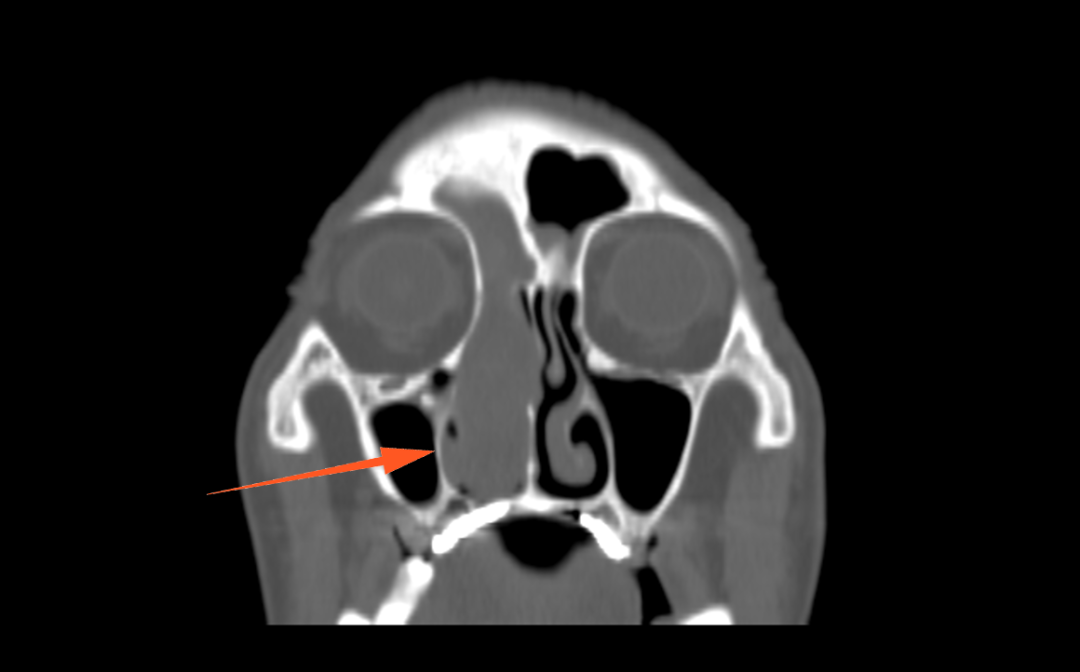

CT显示:右侧鼻腔及额窦、筛窦

又充满了软组织影

无法正常呼吸,伴头痛、嗅觉减退

进一步增强MR显示:鼻腔右侧异常信号影,T1等信号,T2等高信号,DWI高信号,增强后周边强化为主。

蒋主任仔细阅读影像学图像,该患者的肿物在T2相有 “脑回征”,但又不典型,鼻窦骨质也没有明显的增生,肿物已经占满整个右侧额窦窦腔,好在患者额窦气化尚可,肿物未越过瞳孔中线,要彻底清除肿物,需要打开额窦,将窦内软组织完全清理干净并磨除基底部部分骨质再烧灼。